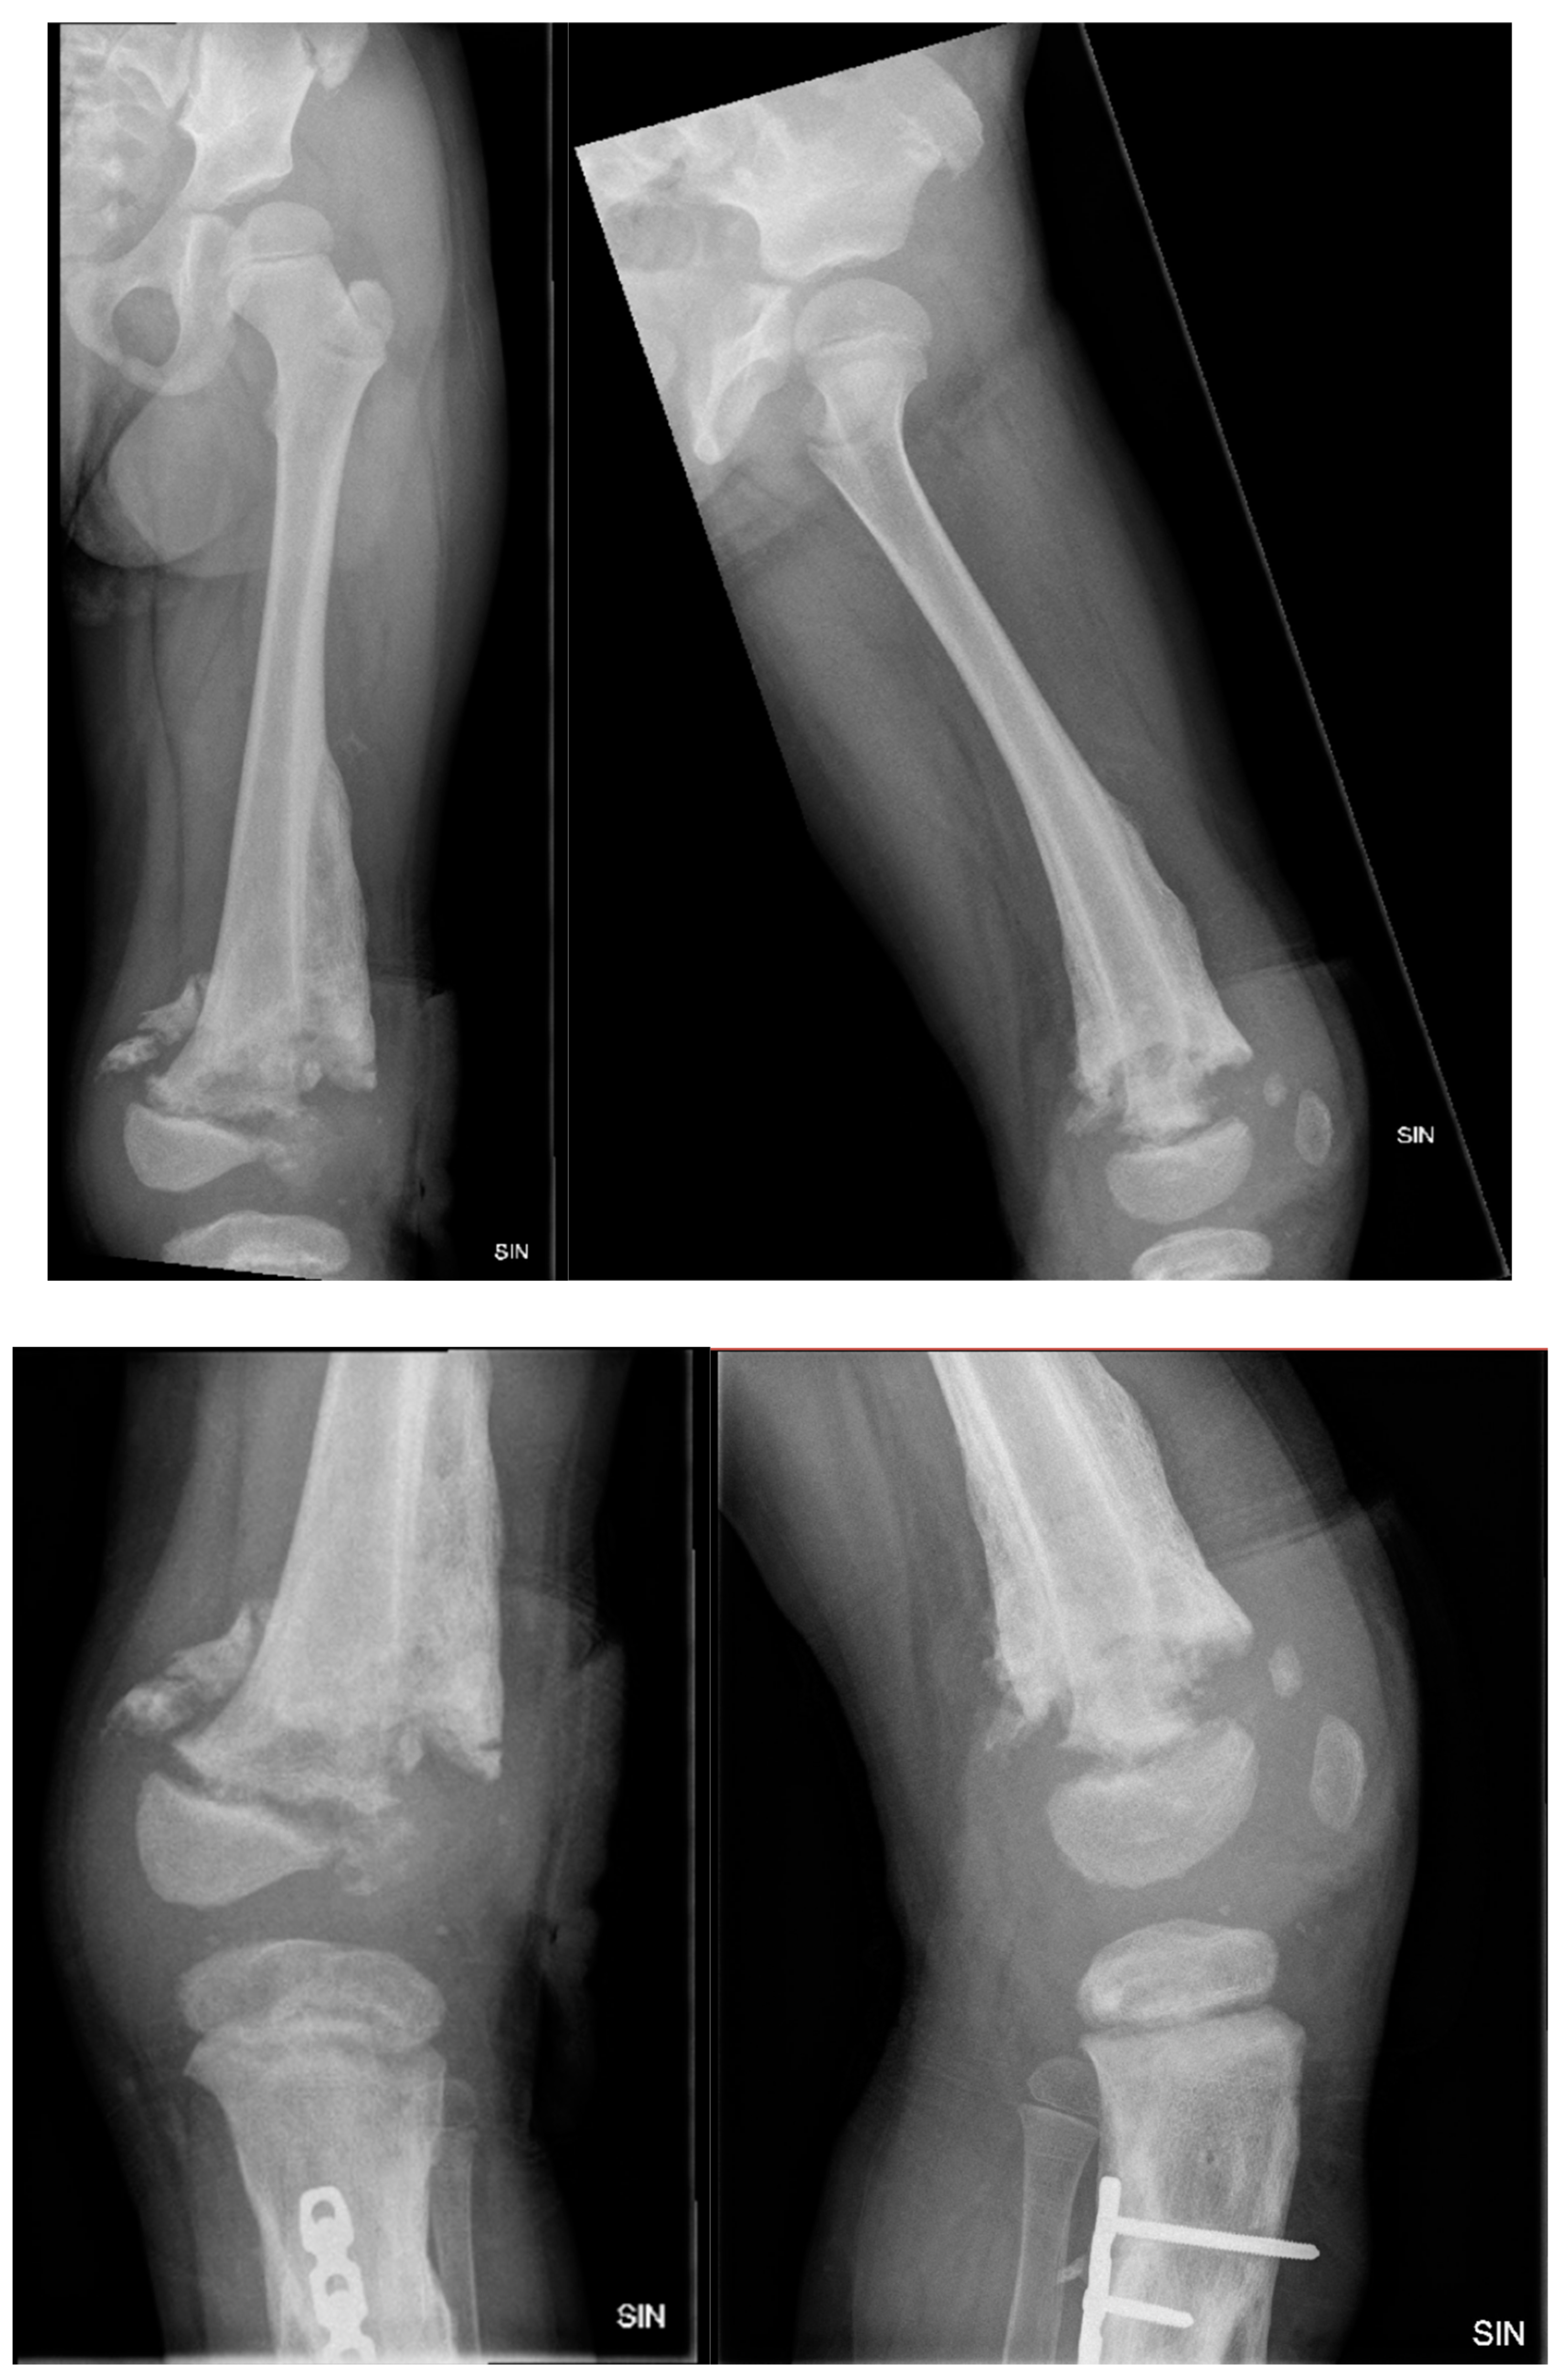

Figure 2. X-ray examination of the left lower leg anterior-posterior (AP) and lateral projections shows marked hyperostosis in soft tissue, moderate angular deformation, and a deformation angle of approximately 15 degrees, with sclerotic hyperostosis type changes around the fracture zone.

Figure 3. X-ray examination of left lower leg in AP and lateral projections shows posttraumatic chronic osteomyelitis of left tibial diaphysis, opening 13 degrees medially after external fixation device application. A cavity (5.8 cm) and soft tissue calcifications are visible.